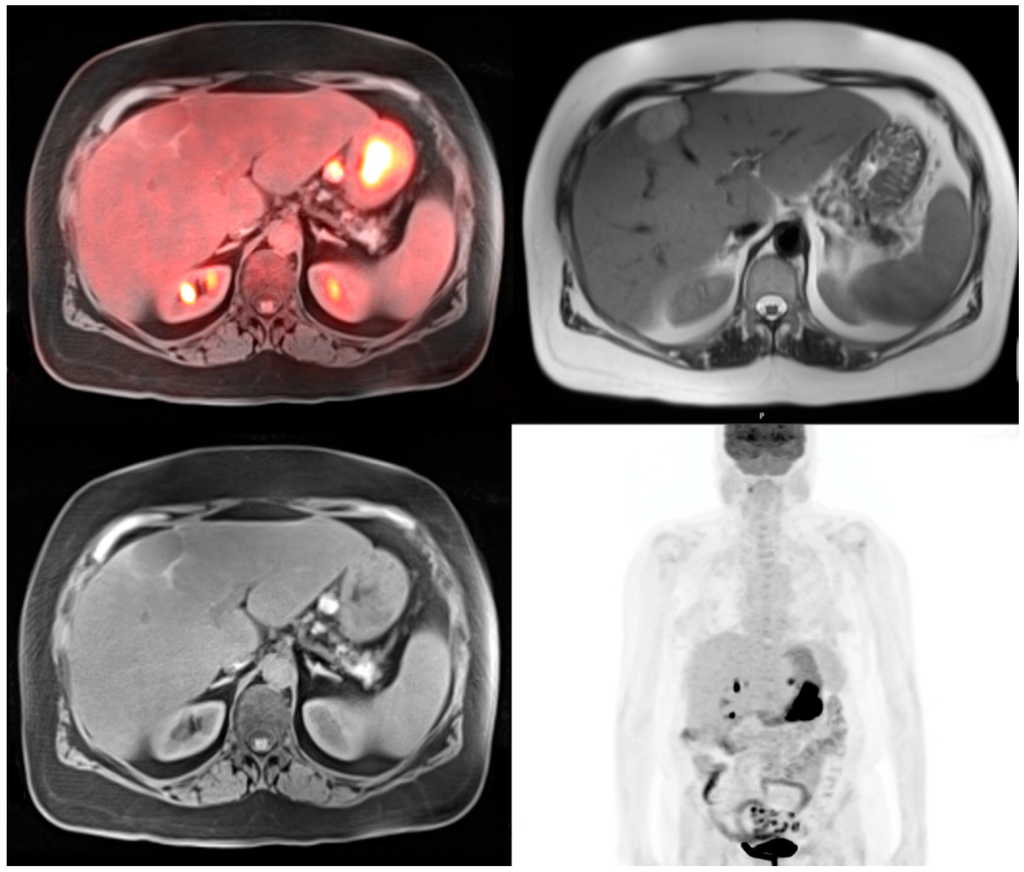

Unenhanced standard MRI sequences including T1 and T2 weighted images can accurately characterize and detect most focal liver lesions and can differentiate between solid and non-solid lesions as shown in Figure 3. Colorectal liver metastases are usually hypovascular, and therefore do not demonstrate significant enhancement with gadolinium based contrast agents [29]. MRI is more advantageous in the assessment of liver metastases when functional imaging like DWI and appropriate hepatobiliary contrast agents are used. Liver specific MRI contrast agents have the highest detection rate for focal lesions if the patient is being evaluated for curative surgical resection [30]. Kang et al. showed that PET-MRI added value to CT scan in 51 patients with colorectal cancer and led to 21% of patient changing therapeutic plans.

Figure 3.

72-year-old male with colon cancer. T1 precontrast transaxial image shows two low signal masses in segment 4B and 5 of the liver (top). T1 post contrast transaxial imaging with gadoxetate disodium reveals heterogenous enhancement of these two masses consistent with metastatic colon cancer (middle). PET-MRI transaxial fusion image confirms malignancy by demonstrating intense FDG activity (bottom). Also note the adjacent benign hemorrhagic cyst with high T1 signal that does not exhibit increased metabolic activity on the fusion images.